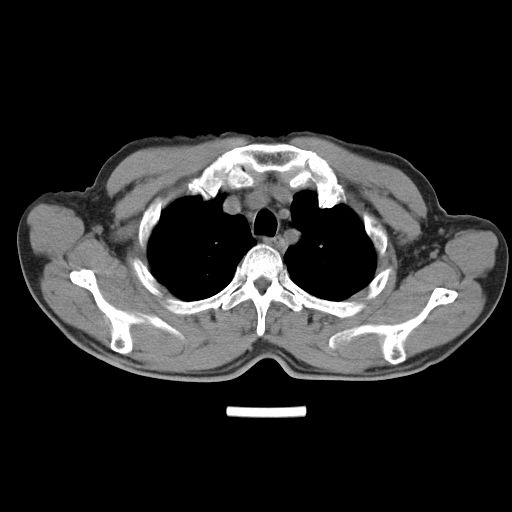

以下是引用心路寻觅在2010-3-1 10:23:00的发言:[br]1、考虑左肺上叶周围型肺癌[br]2、右上肺陈旧性病灶。[br][br][本贴已被 心路寻觅 于 2010-3-1 10:40:18 修改过]

以下是引用shuiyuan在2010-3-1 10:45:00的发言:[br]考虑左肺上叶中心型肺癌伴阻塞型炎症,邻近胸膜受侵。